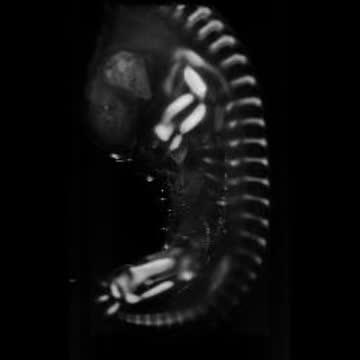

video: Gene expression and 3-D imaging helps to visualize the developing cartilage.avi.

Image: